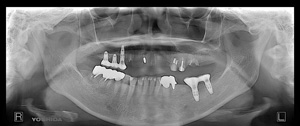

A.T‚³‚ñ@‚U‚QΠ —« Žå•w@Žèp“ú@‚Q‚O‚O‚X”N ‚UŒŽ‚Q‚R“úi‰Îj@ƒm[ƒxƒ‹ƒKƒCƒhŽg—p   Ö¬“à’ÁÖ@•¹—p

@@       ãŠ{   All on ‚V  ’x‰„‰×d @   Rpl Tapered Groovy Rp ‚P‚O mm~‚RA ‚P‚R mm~‚PA ‚P‚U mm~‚P@

@@ @@@    Nobel Speedy Groovy Shorty Rp~‚Q@@Nobel Speedy Groovy Rp ‚WD‚T mm~‚P

@      @   ‰ºŠ{  All on  ‚U  ‘¦Žž‰×d       Rpl Tapered Groovy Np ‚P‚O mm~‚Q        Bmk Rp‚RD‚V‚T mm  ‚WD‚T mm~‚QA@‚P‚O mm~‚Q

@           @– ƒ`ƒ^ƒ“ƒtƒŒ[ƒ€EƒJƒ“ƒ`ƒŒƒo[•â‹­i“Á’j‰„’·ƒuƒŠƒbƒW‚ÅÅI•â’Ô